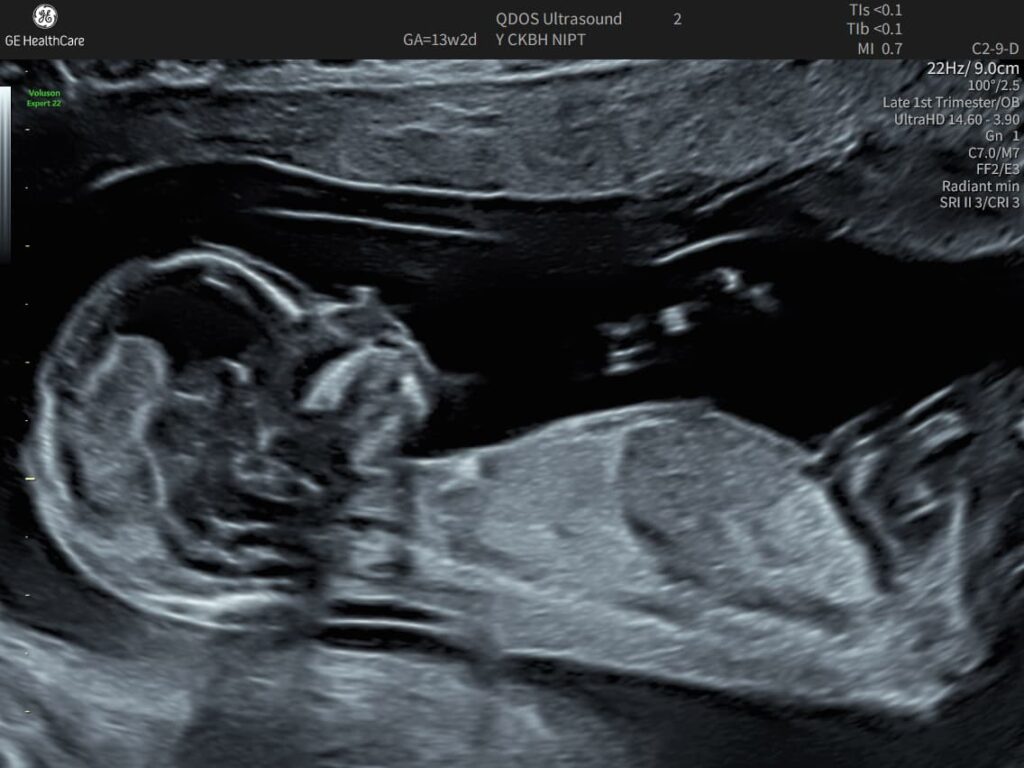

This late first trimester ultrasound is usually the first detailed scan

The 12-14 Week scan is the first true structural check of the fetus, and may be the first time parents see it actually looking like a baby.

The 12-14 Week scan can be especially rewarding for parents as the whole fetus can be visualised on the screen at once, with moving limbs outlined by the amniotic fluid.

For parents who do not wish to have chromosome screening, or who have chosen to have NIPT (Non-Invasive Prenatal Test), this scan is best done between 13 and 14 weeks, to give the most detailed information about the baby’s developing structure.

It is important to know that between 12 and 14 weeks the detail visible varies greatly, for reasons related to both fetus and mother. The baby almost doubles in size, and becomes much busier, which can both help and hinder our examination.